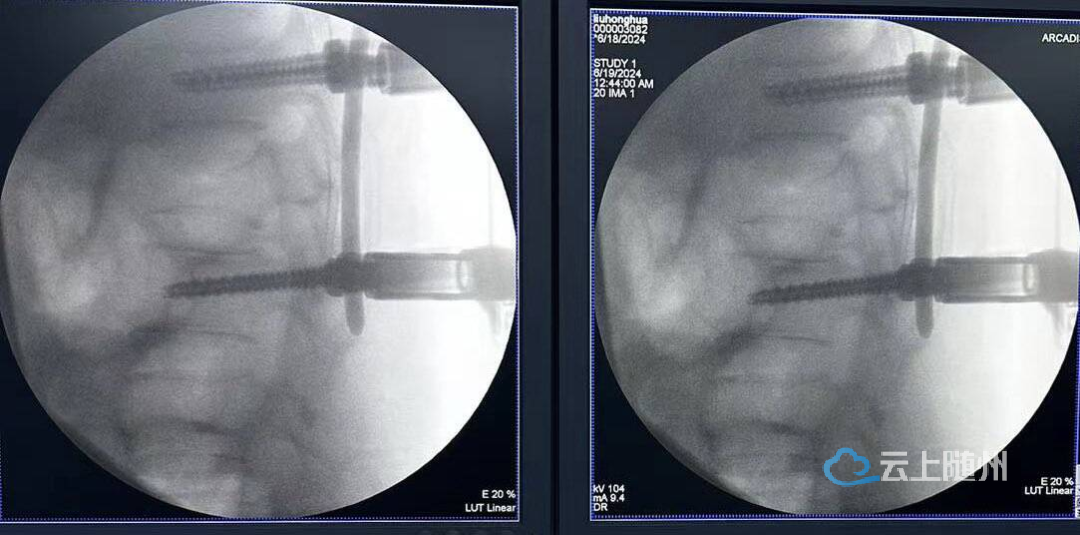

随后,徐三军带领医生杜承文、郭威,为患者顺利实施了经皮椎弓根螺钉内固定术。仅在患者背部作4个2cm左右的小切口,完成置钉、穿棒、复位等手术操作,术程患者的肌肉损伤小、出血少,病椎复位满意,术后患者精神状态良好。经过医护人员的精心照料,患者切口愈合,功能恢复良好,已于近日拆线出院。

据介绍,经皮穿刺椎弓根螺钉内固定术是随州市曾都医院近年来发展起来的脊柱固定微创技术,采用C型臂X线透视下椎弓根精确定位,穿刺植入导丝,逐渐扩张通道,在X线监测下置入椎弓根螺钉,并通过器械行脊柱固定。